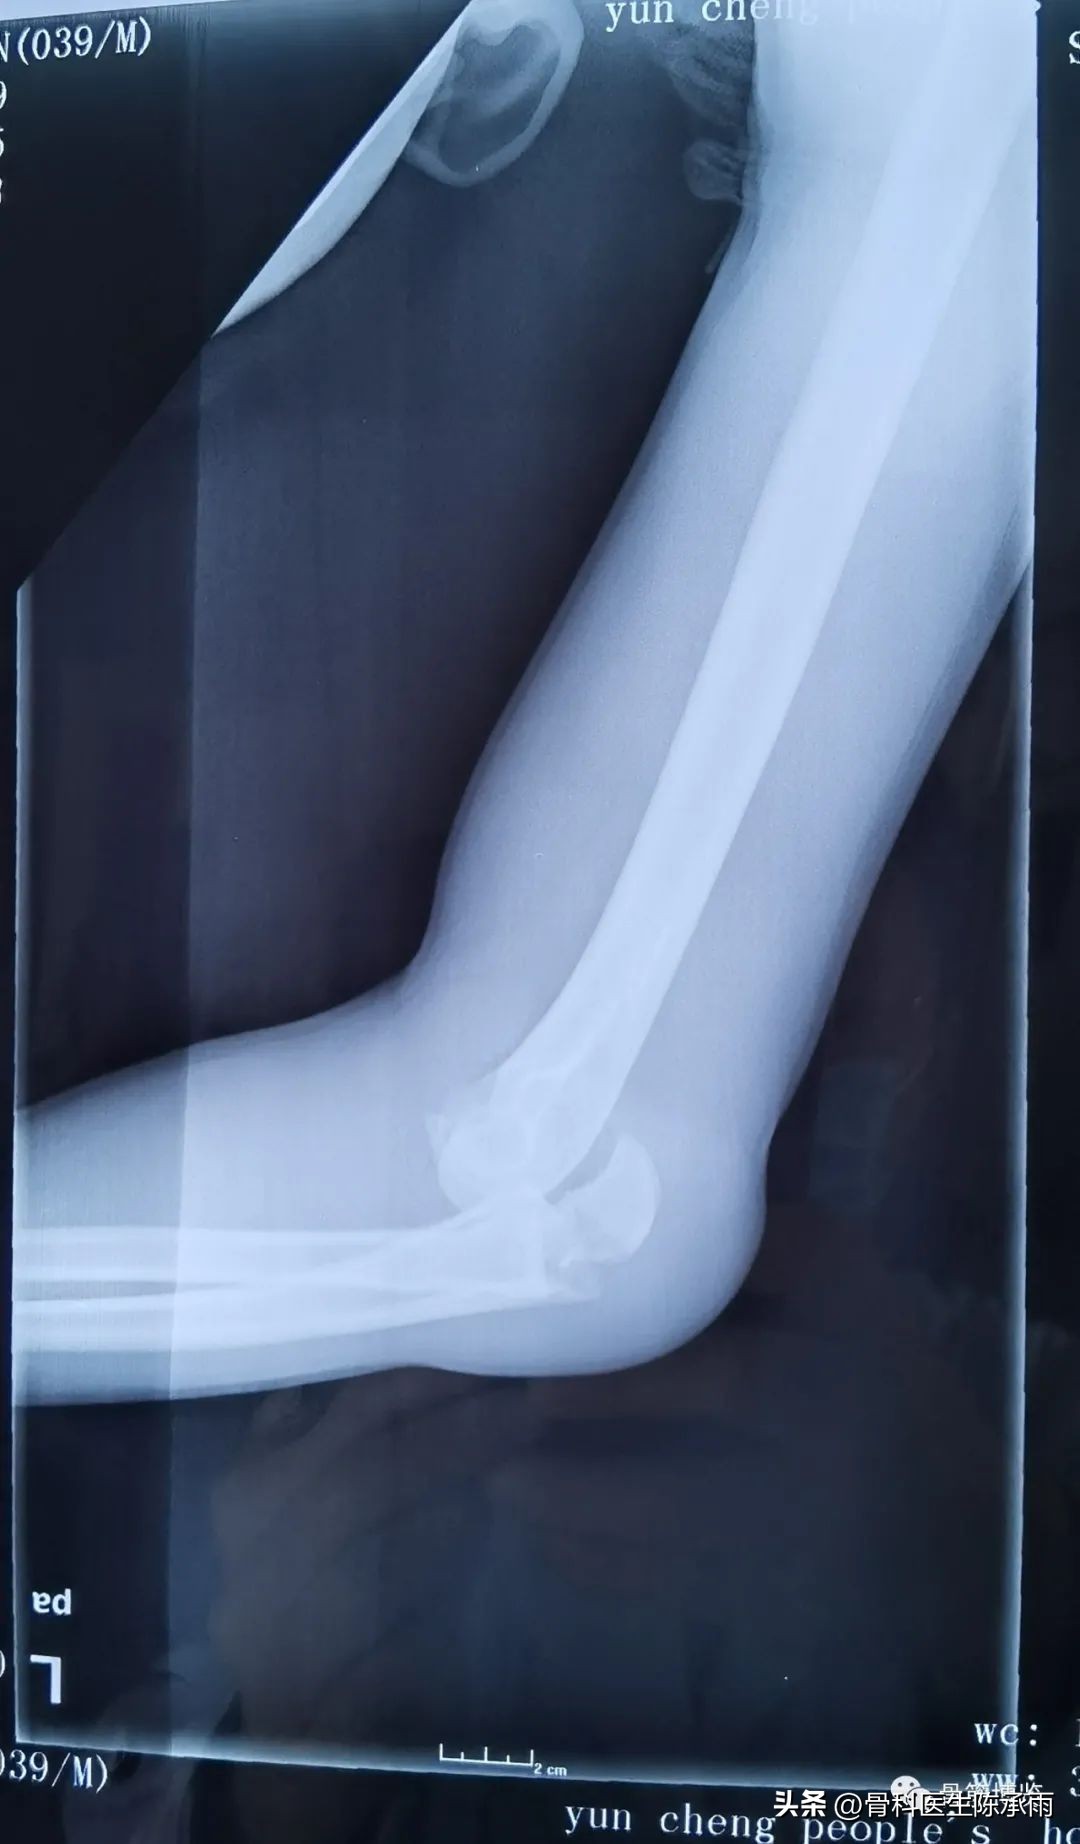

这是最近的1例手术,合并了尺骨鹰嘴骨折,采用后侧入路

术前影像